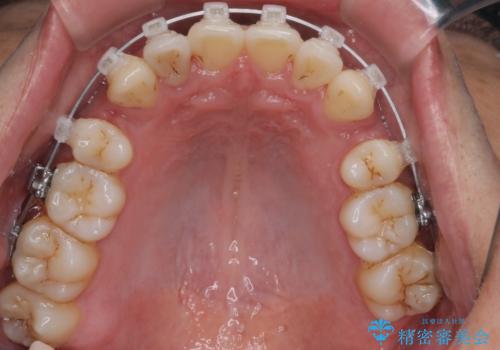

- クリア装置

- 治療計画

叢生量が大きいため、上下顎両側4番を抜歯しました。矯正治療による歯肉退縮の著しい悪化もなく、主訴であるガタつきも改善できました。